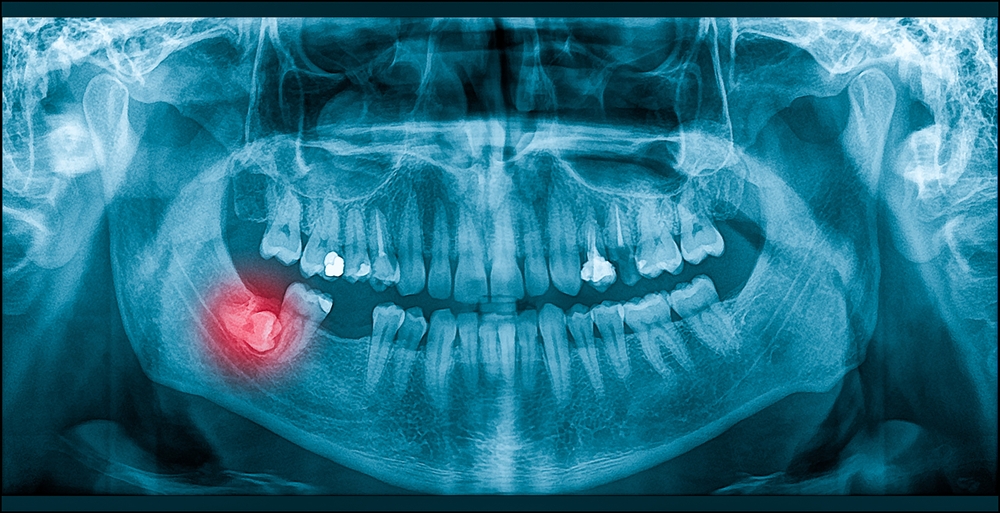

Wisdom teeth can be painful, whether they are erupting or impacted. This pain could come about frequently or spontaneously. A lot of times, the gums around the wisdom teeth will get infected due to a patient's inability to clean all the way into the back of the mouth. This is a condition called pericoronitis. If you have wisdom teeth pain, please come in ASAP to see us so that we can talk about removal options and help preserve the surrounding teeth. In the meantime, you can take over-the-counter pain medication to manage your discomfort.